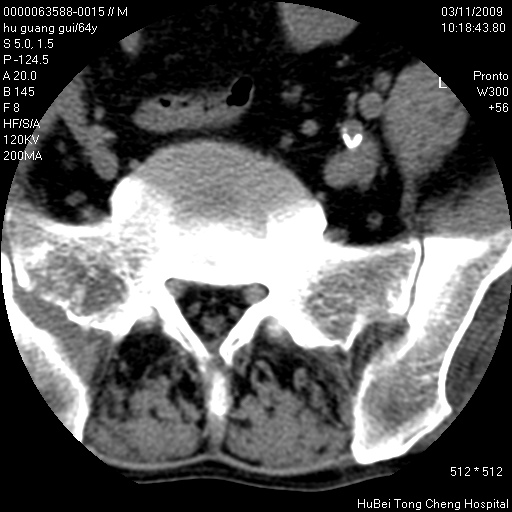

患者 男,64岁。腰痛十余天。(临床未提供其他病史)

临床诊断:腰痛原因待查(腰椎间盘突出症?)。

腰椎间盘ct轴位平扫(层厚5mm,层距4mm),图像如下:

右侧骶骨侧块骨侵蚀,骶髂关节骨性关节面破坏,并见软组织肿块,考虑骨转移瘤可能,进一步检查。

1.腰椎退行性变,腰4—5椎间盘膨出。

2.右侧骶骨侧块骨侵蚀,骶髂关节骨性关节面破坏,并见软组织肿块,考虑:脊索瘤,骨转移瘤可能,进一步检查。